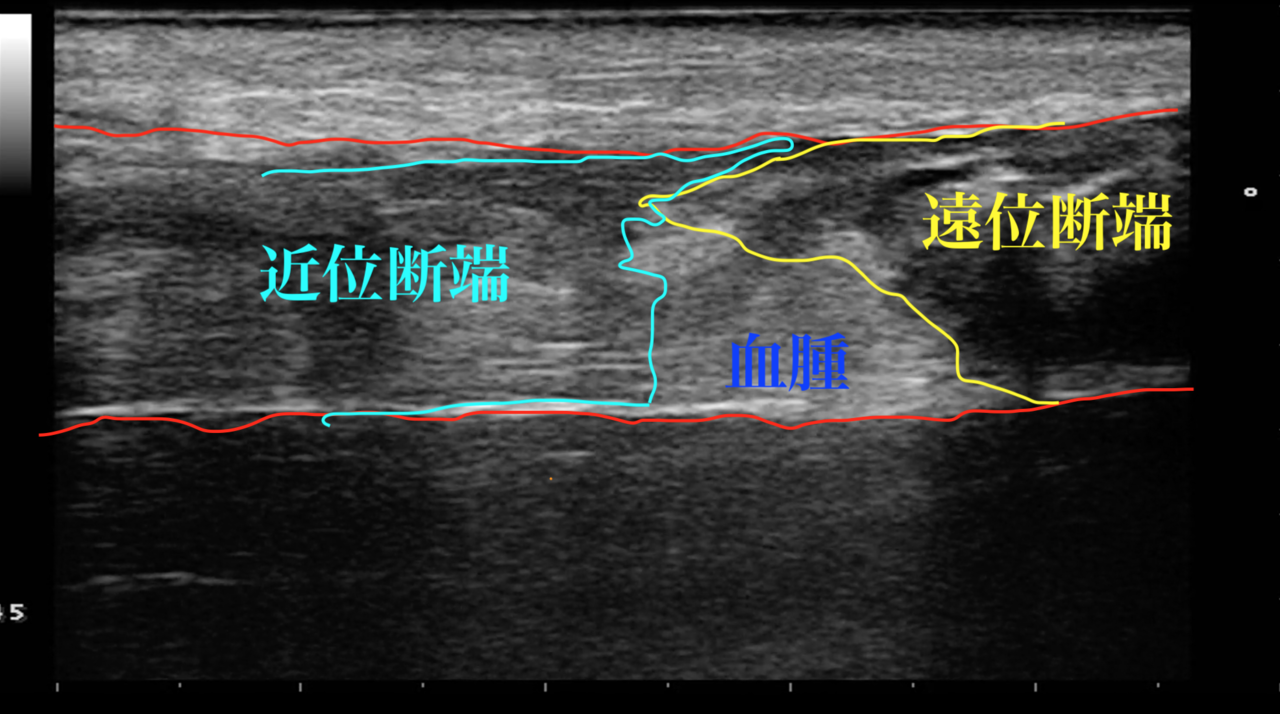

腱断端の接触の様子

断裂が確認できましたら、エコーで腱断端の接触の様子を確認します。

断端が接触していなくてもアキレス腱はつながってきますが、十分に接触していた方が治りが早いです。

十分に接触する角度で的確に固定を行いました。